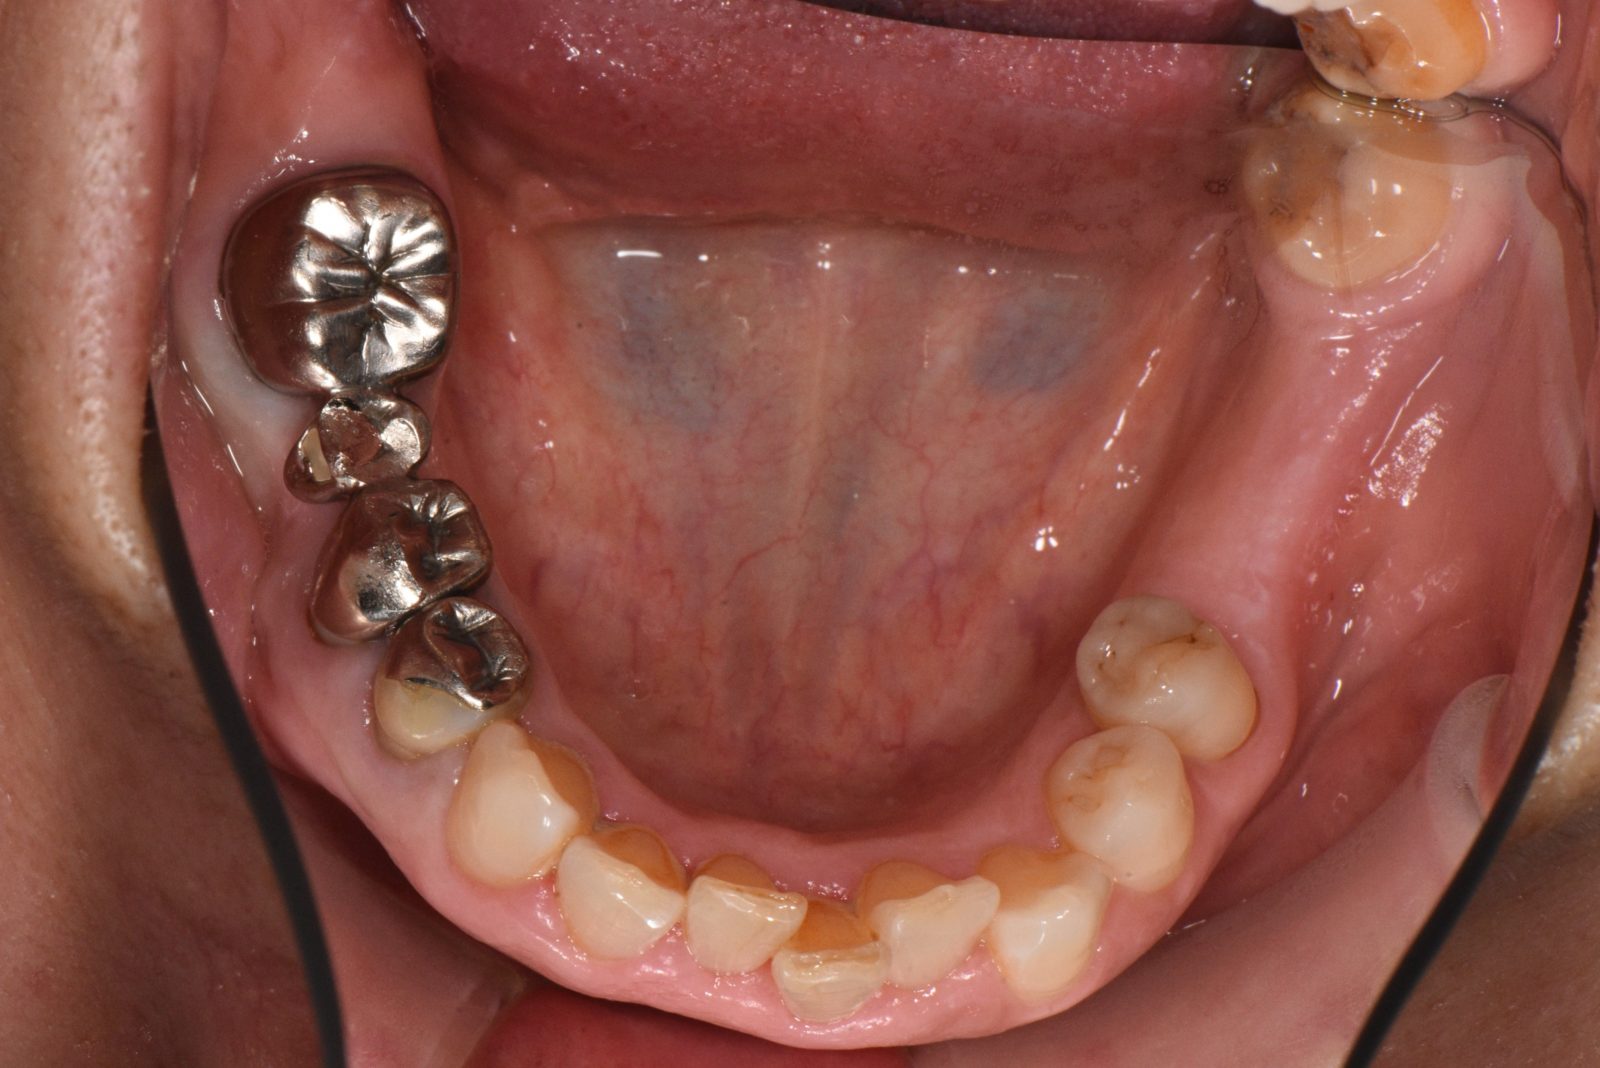

• 治療前

• 治療後